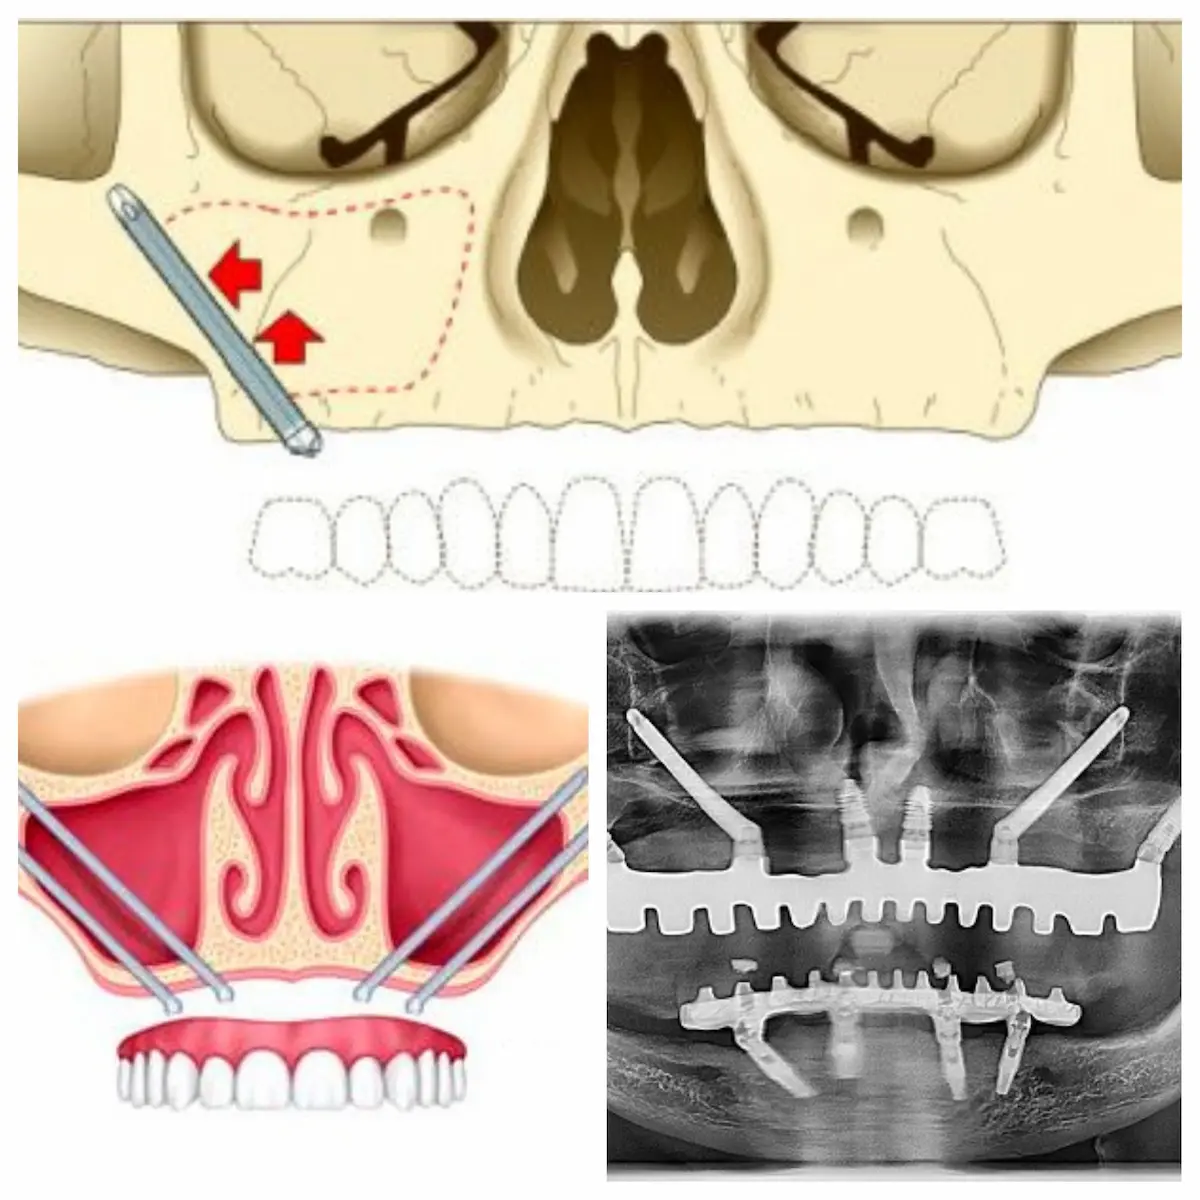

Los implantes cigomáticos son una opción para pacientes que han sufrido una pérdida de hueso dental significativa, ya sea en el maxilar inferior o superior. Esta técnica se utiliza para proporcionar estabilidad a las prótesis dentales sin la necesidad de injertos de hueso tradicionales. Los implantes cigomáticos tienen un tamaño de entre 35-55mm y se colocan lateralmente a través del seno maxilar, alcanzando el hueso cigomático.

A diferencia de los implantes dentales tradicionales, los implantes cigomáticos ofrecen una solución inmediata para restaurar la función y estética dental, sin necesidad de procedimientos de injerto óseo complejos. Al anclar el implante en el hueso cigomático (el pómulo), se asegura una máxima estabilidad y durabilidad de los dientes, lo que resulta en una recuperación rápida y menos complicaciones.